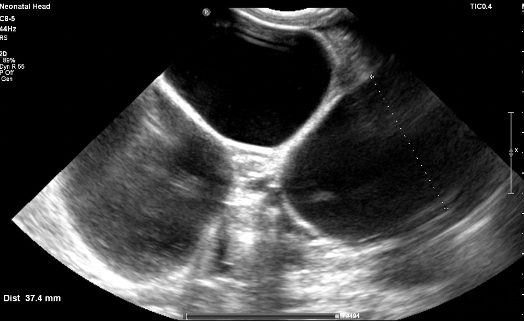

Preterm premature rupture of membranes (pPROM) before 22–24 weeks of gestation is considered previable and poses a high risk to the chances of successful delivery. Multicystic dysplastic kidney (MCDK) is the most common form of dysplasia of this organ, usually affecting 1 kidney. A prenatal suspicion of MCDK requires escalation of the clinical process to a reference center qualified and equipped for further diagnosis and treatment. We present a unique case of prenatal pPROM at 19 weeks of gestation in a pregnancy complicated by fetal MCDK as an interesting obstetric and neonatal patient story. We have not found any published evidence on the impact of coexisting fetal congenital malformations on a pregnancy affected by previable pPROM.

Balasundaram M, Chock VY, Wu HY, Blumenfeld YJ, Hintz SR. Predictors of poor neonatal outcomes in prenatally diagnosed multicystic dysplastic kidney disease. J Perinatol 2018;38(6):658-64.

Pettit S, Chalmers D. Neonatal multicystic dysplastic kidney with mass effect: A systematic review. J Pediatr Urol 2021;17(6):763-8.